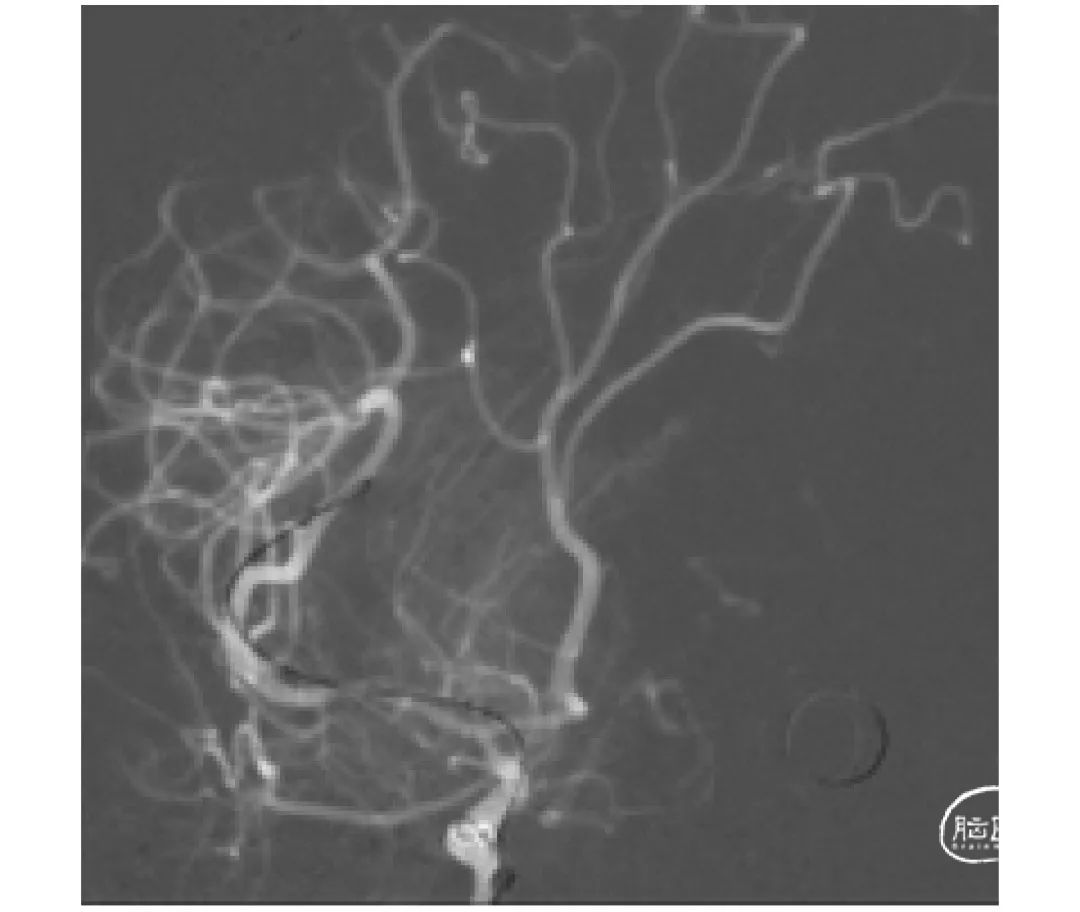

上海心玮医疗科技股份有限公司(股票代码:06609.HK)成立于 2016 年,公司致力于提高创新医疗技术的可及性,守护生命健康。六年时间,心玮医疗在神经介入领域开拓性地打造了国内首个卒中治疗及预防一站式解决方案,拥有从急性缺血性卒中和神经血管狭窄治疗、缺血性卒中预防、出血性卒中治疗到介入通路器械的全产品管线,申请专利超过 100 项,产品年产能超过 15 万件,销售渠道覆盖国内超过 30 个省(含直辖市和自治区)的 1400 多家医院。